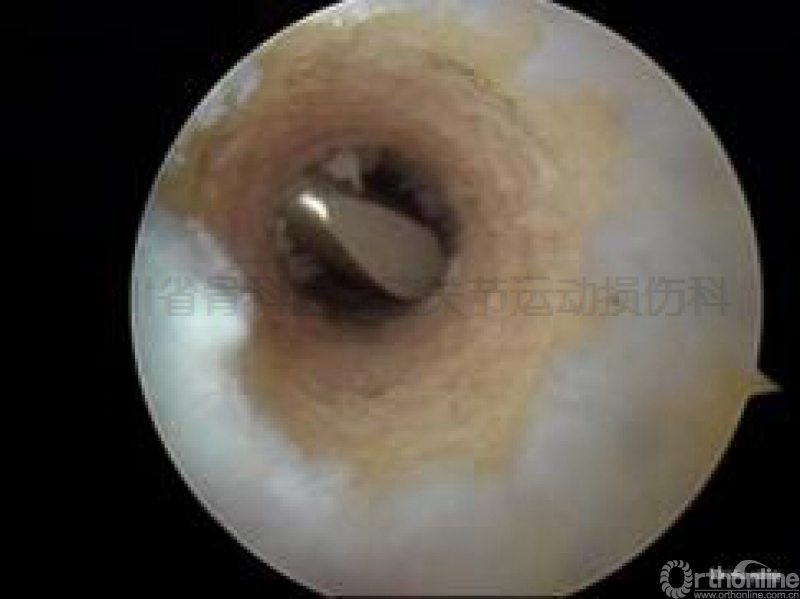

但也有标本被发现横穿钉穿过了腘肌腱及外侧副韧带,甚至穿到了股骨外髁边缘的关节软骨上(图示三)。

图示三尸体试验显示RigidFix双鞘管在经前内入口安全区的击入点。

a点标示为腘肌腱;b点标示为股骨外髁下缘的关节软骨。

不幸的是,一个鞘管穿过了腘肌腱,一个穿在了关节软骨上。